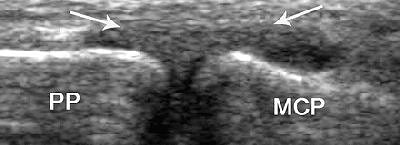

![]() |

| Strain of the radial collateral ligament. The left side of the images is distal. Above, coronal US scan of the thumb shows a thickened elongated radial collateral ligament (R). Below, coronal US scan of the contralateral thumb, obtained for comparison, shows a normal radial collateral ligament (arrows). "US Diagnosis of UCL Tears of the Thumb and Stener Lesions: Technique, Pattern-based Approach, and Differential Diagnosis," Ebrahim FS, et al. RadioGraphics 2006;26:1007-1020. |

In radial side ligament injury, look for distinctive patterns of instability, they stated. A disrupted UCL, along with dorsal capsular tears, is likely to result in combined radiovolar subluxation. Disruption of the radial collateral ligament is more likely to produce a rapid sequence of joint instability and, ultimately, degenerative disease.